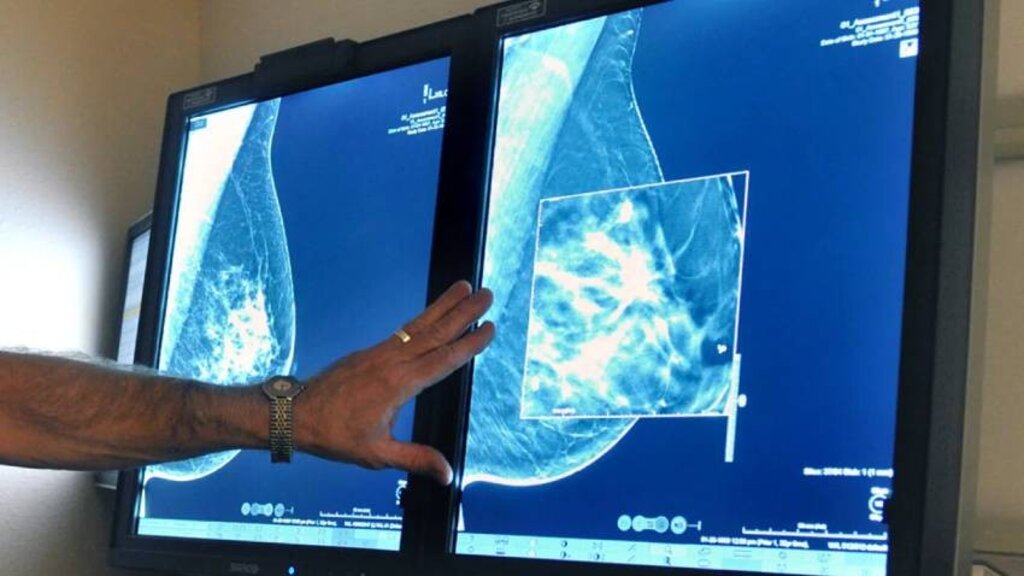

Карциномът на млечната жлеза е най-често срещаното онкологично заболяване при жените, затова го определят като социално значимо, засягащо пациентки от различни възрасти. В Световен мащаб всяка година се откриват повече от 2 милиона случая на рак на гърдата. Добрата новина обаче е, че ако бъде открит навреме, над 90% от жените успяват да достигнат над 5-годишна преживяемост.

Всяка година около 4 хиляди българки са ново диагностицирани с рак на гърдата. Това означава, че всяка осма жена у нас е застрашена от проява на коварната болест. Ракът на гърдата също е сред заболяванията, които се появяват във все по-ранна възраст. Около 800 от новите случаи всяка година са при жени ненавършили 50 години – пояснява д-р Гергана Георгиева, специалист по образна диагностика към болница "Аджибадем Ситиклиник".

"Има достатъчно добри технологии за ранна диагноза, също има много видове лечения и всичко това помага при преодоляването на този проблем. Все по-често жените у нас идват и са информирани колко често и кога да правят своите профилактични прегледи. Това, което ние препоръчваме е, мамография да се прави след 40-годишна възраст, на всяка втора година, а ехографията да се провежда след 25-годишна възраст, но всяка година. За жалост възрастта, в която се открива рак на гърдата наистина пада, имаме пациентки в доста ранна възраст, при които изобщо не очакваме да са засегнати, но откриваме находки на злокачествено заболяване. Затова жената след 25-ата си година трябва да правят ехография на гърдата. Дори и идвайки на профилактичен преглед, жените са притеснени от срещата с лекаря, но притеснителното в случая не следва да е самият преглед, а да не бъде пропуснато нещо и да не бъде назначена подходяща терапия" – казва д-р Георгиева.

Голяма част от отговорността за откриване на рака на млечната жлеза пада тъкмо върху специалистите като д-р Гергана Георгиева. В своята практика тя разполага с висок клас 2D и 3D апарати за мамографски преглед, като всичко се прави спрямо индивидуалния случай на пациентката. "Специалистите по образна диагностика сме хората, които могат да открият евентуален проблем в гърдата, но от там нататък ние работим заедно с цяла съвкупност от медицински специалисти" – казва д-р Георгиева: